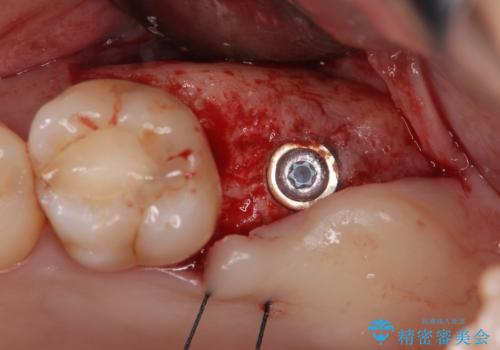

精査した結果、上顎奥歯は歯が割れてしまっており、根管治療ではなく抜歯の対象でした。

歯の抜去後、しっかりと咬合機能を回復するためインプラントを用いた治療を行っていきます。